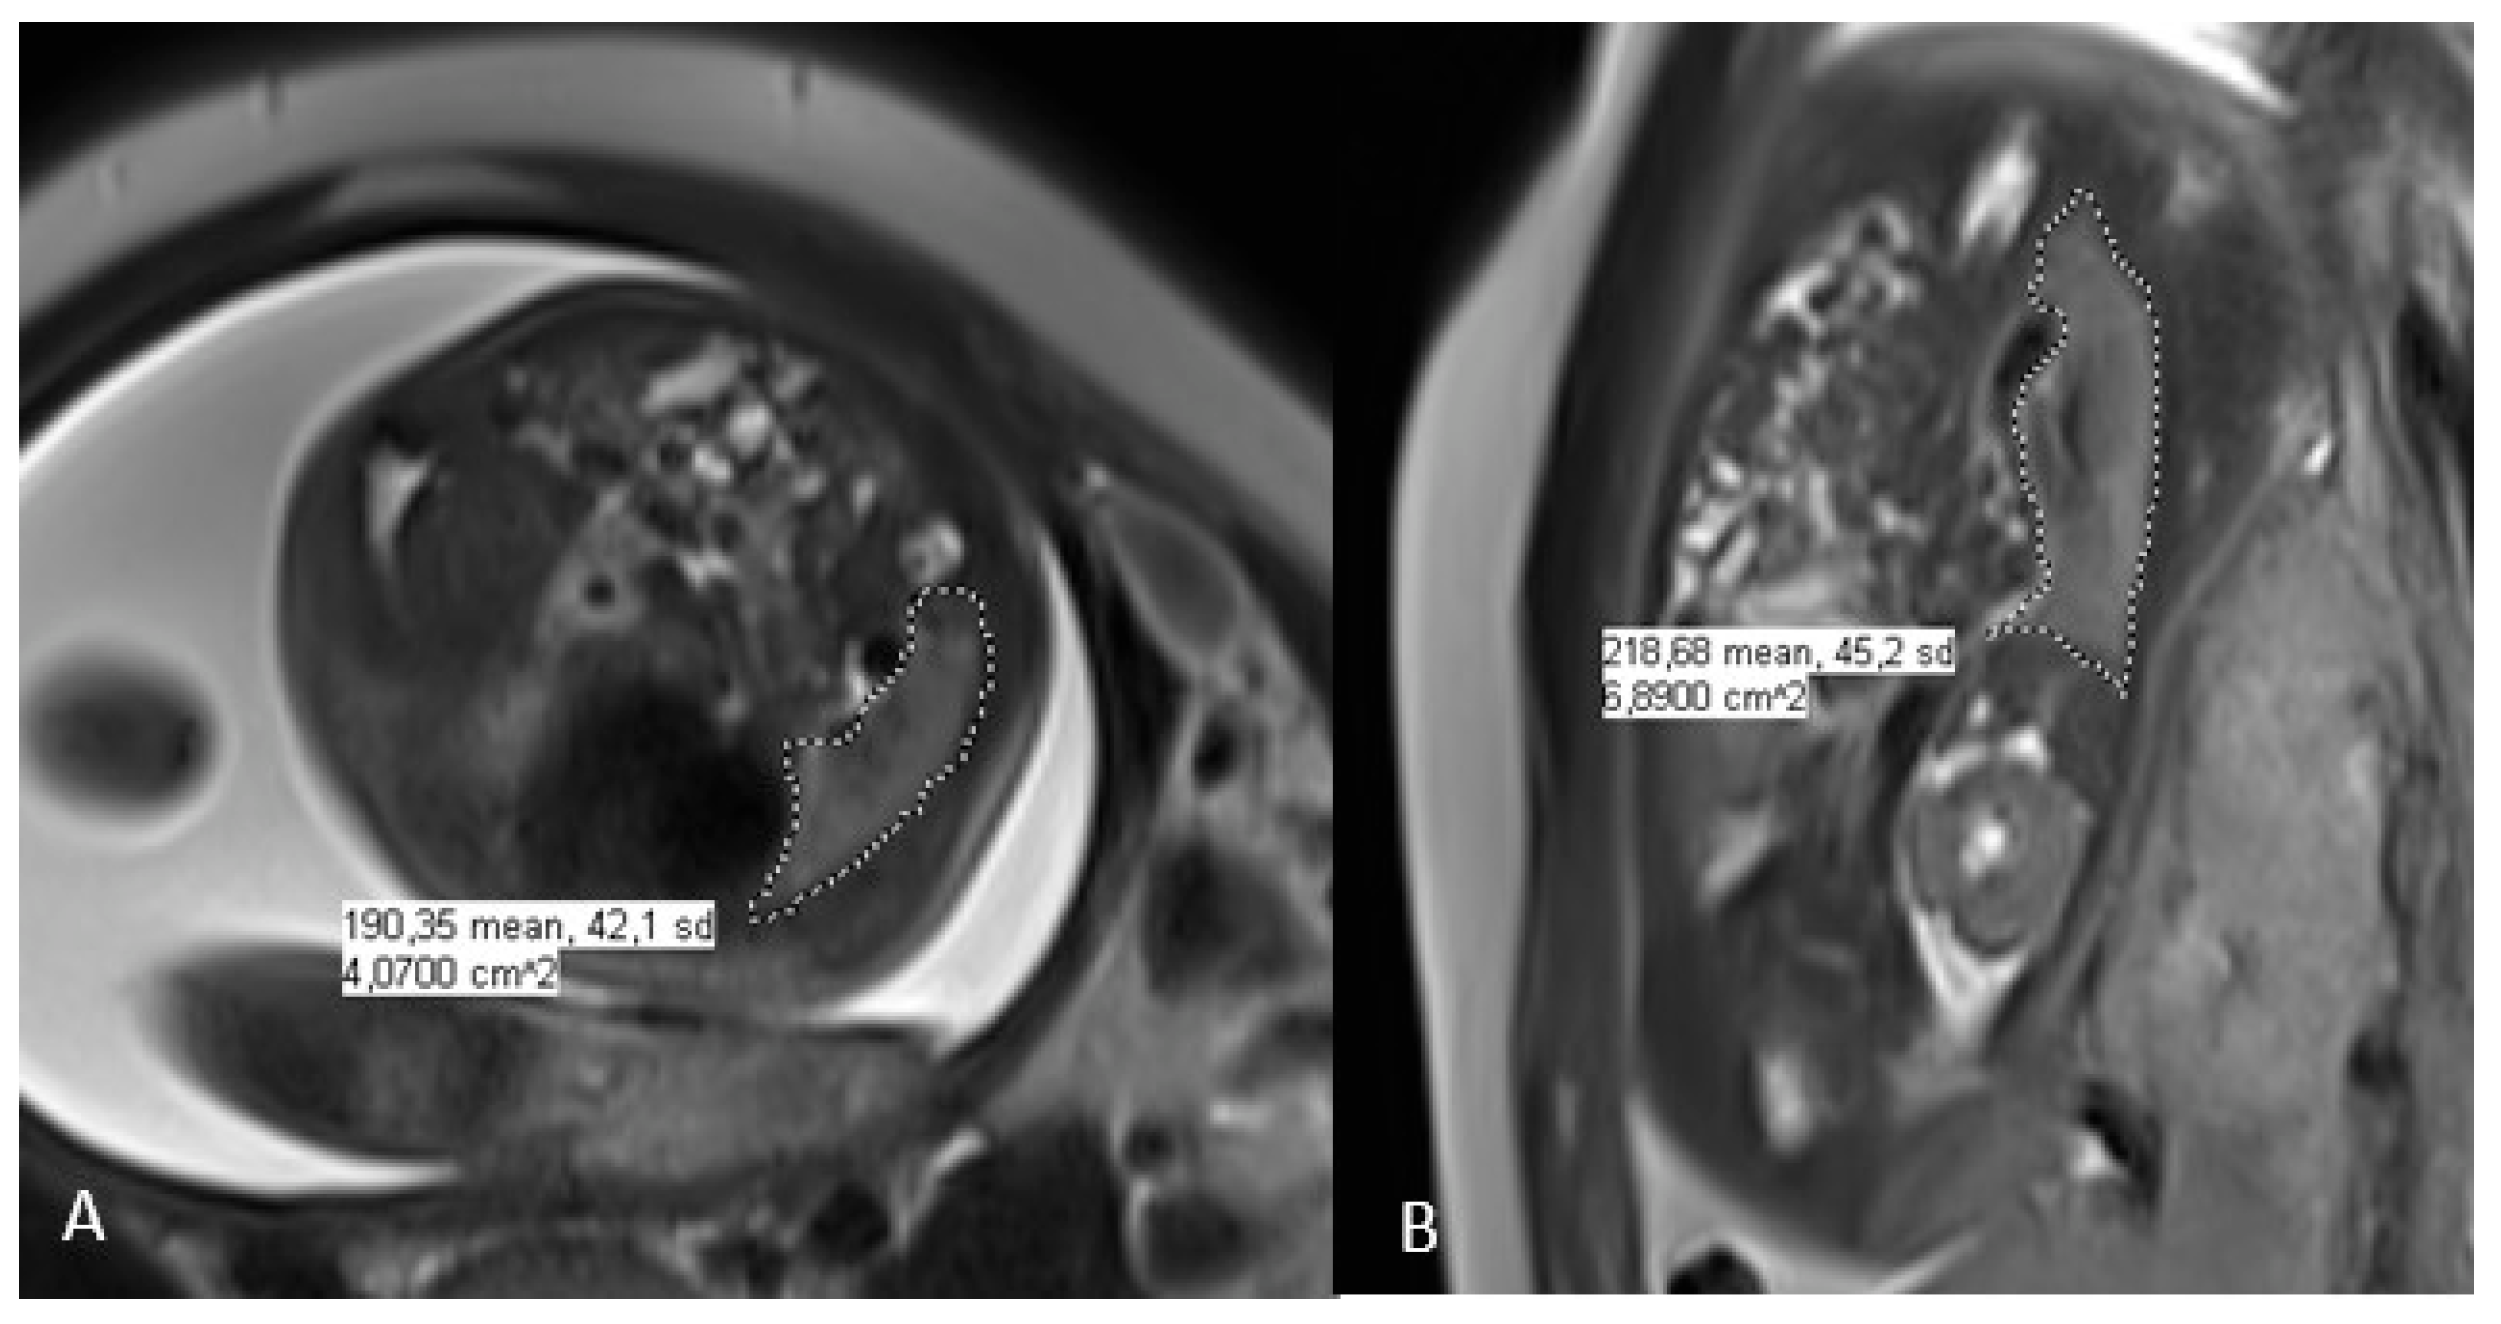

Fetal MRI performed at 31 wk of GA. A, axial T2‐weighted image showing Nutmeg Lung Fetal Mri “nutmeg lung” describes the fetal mri appearance of pulmonary lymphangiectasia with tubular structures radiating from the hila. This was primarily in patients with chd (hlhs) with pulmonary vein congestion on fetal echo. Prenatal finding of “nutmeg lung” or fetal pulmonary lymphatic disorder was identified in all five patients on fetal mr imaging, and in. We describe the nutmeg lung appearance. Nutmeg Lung Fetal Mri.